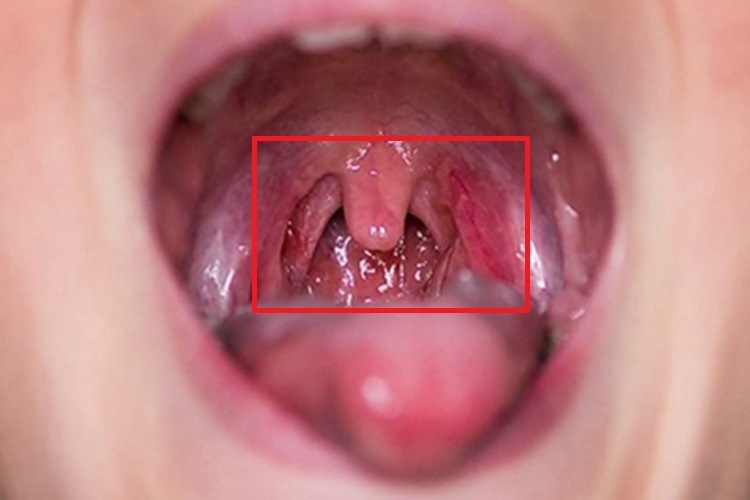

急性咽炎检查时可见咽部黏膜有不同程度的红肿,表面充血、发红,并有多个血丝出现,黏膜表面可见黄白色点状渗出物,自觉咽部有干燥、灼热、肿胀以疼痛。